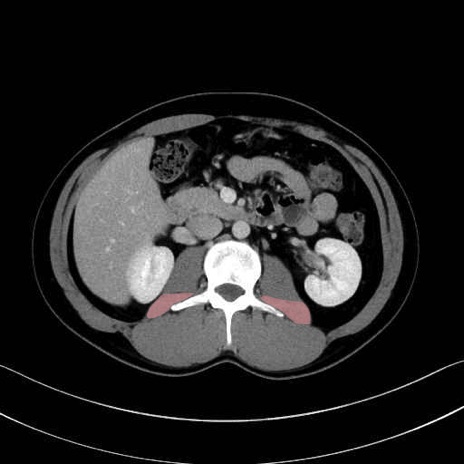

腰方形筋(quadratus lumborum muscle)のCT画像の解剖

腰方形筋 (Quadratus lumborum)